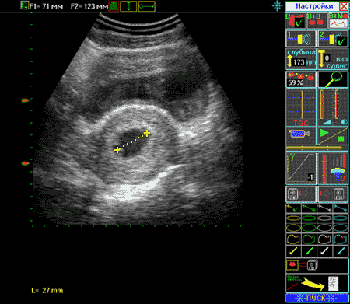

1. Проведение измерений

2. Фиксация в протоколе результатов измерений

3. Наблюдение результата расчета

БПР головки плода = 78 mm

Средний диаметр брюшной полости плода = 82 mm

Длина окружности брюшной полости плода = 258 mm

Средний диаметр грудной клетки плода = 72 mm

Длина бедренной кости плода = 59 mm

Длина голени плода = 52 mm

Длина плеча плода = 54 mm

Длина предплечья плода = 49 mm

Толщина плаценты = 30 mm